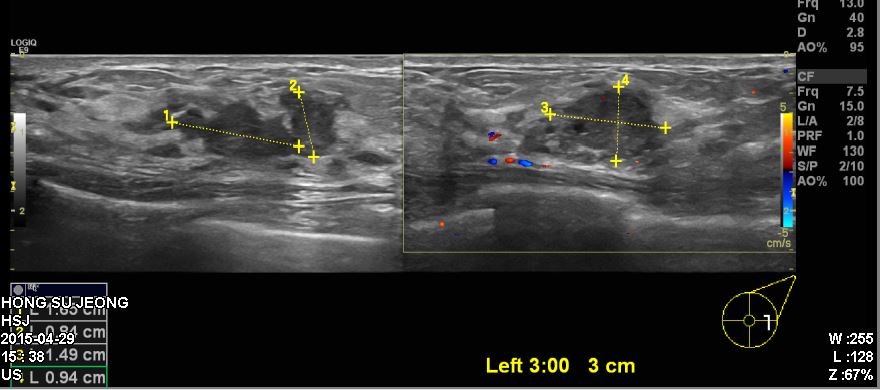

건강검진상 이상 소견으로 내원하신 50대 여성분으로 좌측 침윤성 유관암 진단

되었습니다.